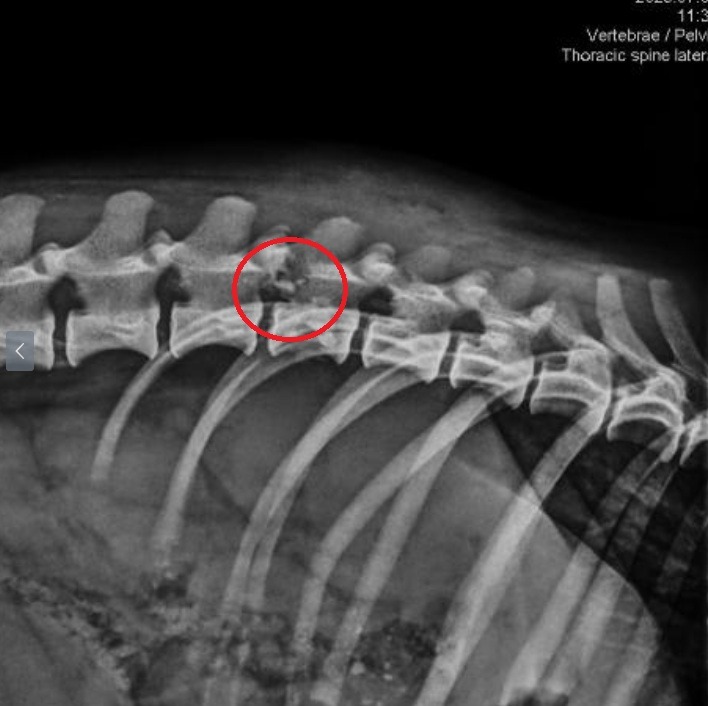

Der kleine Hundebub wurde von einer älteren Dame zu Ana gebracht. Seine Hinterpfoten sind gelähmt – wir vermuteten zunächst, dass er angefahren wurde. Zuerst kam er in Arad in die Tierklinik, und wir standen vor der schwierigen Frage, wie es weitergehen soll.

Jetzt befindet sich Bob in einer Tierklinik in Ungarn. Leider ist noch ungewiss, ob er jemals wieder seine Hinterbeine bewegen kann.